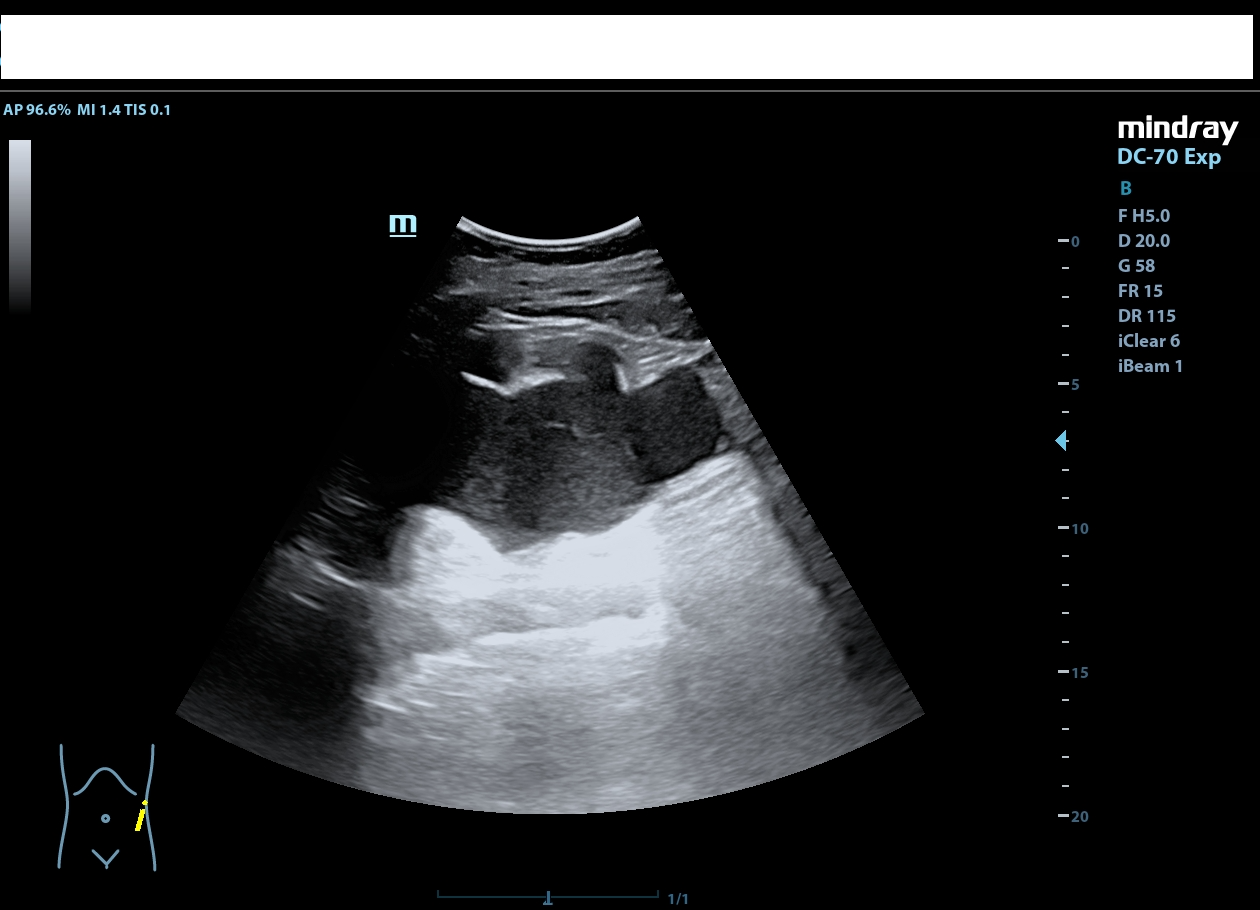

Descripción de los hallazgos ecográficos y las imágenes más relevantes para la resolución del caso

Riñón derecho de ecoestructura conservada, con dilatación pielocalicial grado I. Riñón izquierdo con adelgazamiento cortical y ureterohidronefrosis grado IV, sin poder localizarse el origen de la obstrucción, ausencia de jet ureteral izquierdo. Hallazgos sugestivos de síndrome de la unión pieloureteral.